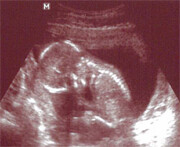

Ahoj holky,v pondělí mě čeká další ultrazvuk, abychom zjistili v kolikátém jsem vlastně týdnu, poslední menstruace byla zběsilá.Nedávno jsem psala do sekce "Nemoci dětí", že jsem neprodělala žádnou dětskou nemoc. Takže si musím dávat bacha na dětské kolektivy... jenže, tento víkend hlídám švagrové dvě malé děti. Aby toho nebylo málo, je tu kočka, která je normálně v pohodě, je očkovaná, ale zrovna tento víkend musela mít nějaké problémy a zvracela a zvracela. Naštěstí starší z holčiček se o ni starala sama. No a dalším testem byla sobota a taneční závody... 400 dětí v jedné hale, celý den. Tak teď doufám, že je vše ok a nic jsem nikde nechytla. Prcky mám ráda, ale už se těším do mého "izolovaného" života.